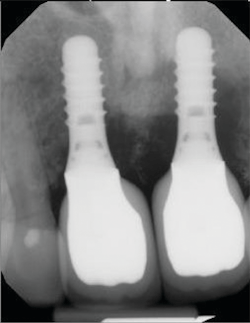

Symptoms of peri-implantitis may include bleeding on probing, deep probing depths, edema, redness, suppuration, and radiographic bone loss (figures 4 and 5).

One of the most perplexing causes of peri-implantitis is residual cement being left behind unknowingly. The cement is often difficult to feel with an explorer and not always visible radiographically. This happens often enough that the problem has earned its own name, “cementitis,” and it can create an infection severe enough to cause the implant to fail (figures 6–8).